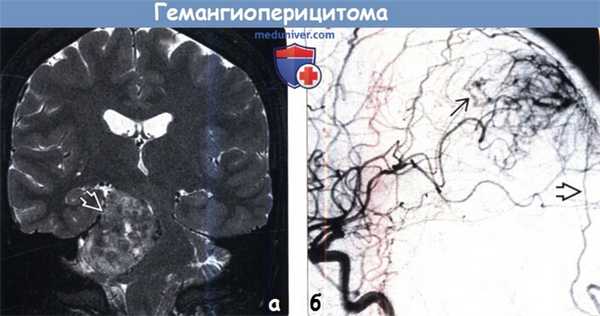

(а) МРТ, Т2-ВИ, режим подавления сигнала от жира, корональный срез: определяется крупное гетерогенное объемное образование, сконцентрированное в правом мостомозжечковом углу и имеющее связь с твердой мозговой оболочкой. При резекции была диагностирована гемангиоперицитома.

(б) ЦСА, контрастирование ВСА, боковая проекция: определяется артериовенозное шунтирование с ранним венозным дренированием. Также наблюдается дополнительный питающий сосуд — ветвь затылочной артерии. Для гемангиоперицитом характерно смешанное кровоснабжение из сосудов твердой и мягкой мозговых оболочек. Часто полезно проведение предоперационной эмболизации.